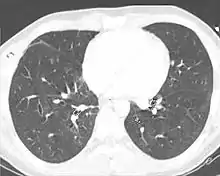

A chest CT scan revealing pulmonary contusions, pneumothorax, and pseudocysts

Computed tomography (CT scanning) is a more sensitive test for pulmonary contusion,[6][33] and it can identify abdominal, chest, or other injuries that accompany the contusion.[38] In one study, chest X-ray detected pulmonary contusions in 16.3% of people with serious blunt trauma, while CT detected them in 31.2% of the same people.[45] Unlike X-ray, CT scanning can detect the contusion almost immediately after the injury.[43] However, in both X-ray and CT a contusion may become more visible over the first 24–48 hours after trauma as bleeding and edema into lung tissues progress.[46] CT scanning also helps determine the size of a contusion, which is useful in determining whether a patient needs mechanical ventilation; a larger volume of contused lung on CT scan is associated with an increased likelihood that ventilation will be needed.[43] CT scans also help differentiate between contusion and pulmonary hematoma, which may be difficult to tell apart otherwise.[47] However, pulmonary contusions that are visible on CT but not chest X-ray are usually not severe enough to affect outcome or treatment.[37]